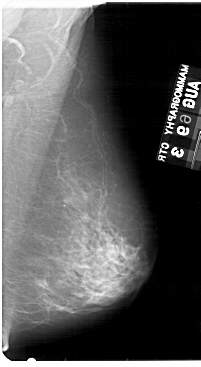

A_1954_1.RIGHT_MLO

RIGHT_CC LINES 5416 PIXELS_PER_LINE 2911 BITS_PER_PIXEL 12 RESOLUTION 43.5 NON_OVERLAY